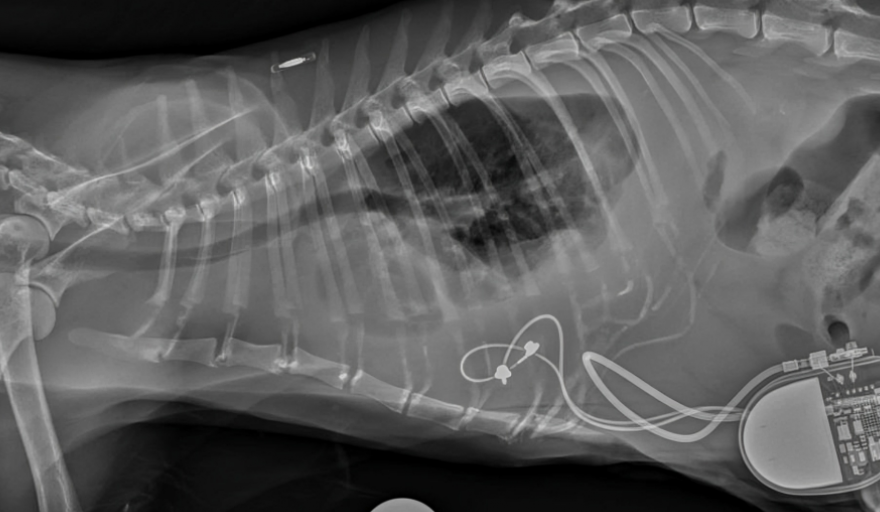

Un estudio reciente demostró que la implantación de un marcapasos epicárdico en felinos se asocia con una baja tasa de complicaciones y una mejor calidad de vida de los gatos que padecen enfermedades cardíacas graves.

Un nuevo estudio dirigido por el Royal Veterinary College (RVC) ha demostrado que la implantación de marcapasos epicárdicos (EP) mejora la calidad de vida de los gatos que padecen enfermedades cardíacas graves.

El uso de la implantación de EP para facilitar la estimulación cardíaca artificial (ACP) resolvió eficazmente los síntomas, incluida la frecuencia cardíaca anormalmente lenta (bradiarritmia) en los gatos.

Si bien este tipo de cirugía generalmente se ha reservado para gatos que presentan síntomas como pérdida de conciencia (síncope), letargo o congestión cardíaca, el estudio ahora confirma que el marcapasos epicárdico es una oportunidad quirúrgica beneficiosa, lo que resulta en una vida más larga y mejor para estos gatos.

El equipo de investigación, dirigido por el Dr. Matteo Rossanese, profesor titular de cirugía de tejidos blandos en animales pequeños y codirector de cirugía de tejidos blandos en el RVC, examinó las complicaciones y los resultados en gatos después de la implantación mediante la revisión de los registros médicos de 39 gatos de cuatro hospitales veterinarios del Reino Unido.